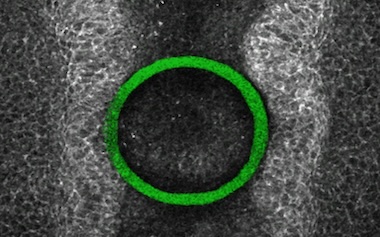

Two-photon bioprinting was identified as the route to crating the 3D shapes with high positional and structural accuracy directly in chick embryos, crosslinking a i3D polymer introduced into the area of interest. When exposed to a strong laser, the liquid transforms into a spring-like solid attached to the growing spinal cord of the embryos and deformed by the mechanical forces produced by the embryo's cells, said the project.

"We adapted i3D bioprinting to create elastic, compliant shapes anchored to the closing neural folds, such that their deformation serves as a read-out of forces generated by medial apposition of the neural folds. We refer to these structures as intravital mechano-sensory hydrogels (iMeSHs)."

A combination of live imaging and mechanical modelling was used to monitor the deformation of the new structure during embryo development. This let researchers observe the forces involved in normal growth of the neural tube, and also start to investigate whether pharmaceutical intervention might increase positive forces or decrease negative ones enough to help prevent malformations such as spina bifida.